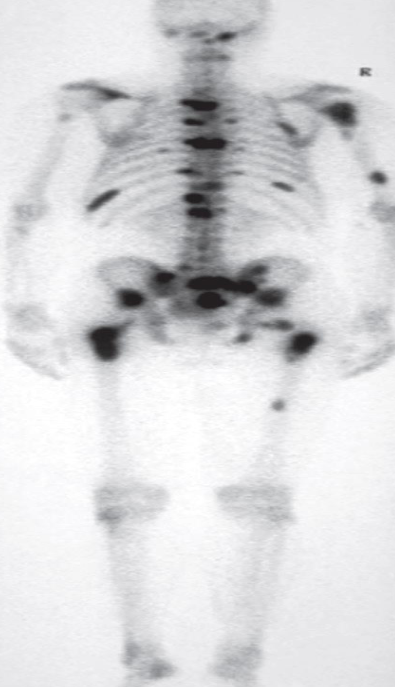

A. Give the name of the used imaging modality

SCINTIGRAPHY /RADIONUCLIDE BONE SCAN

B. What is the most probable diagnosis ? Metastasis

C. Describe the abnormality. Multiple areas of increased uptake